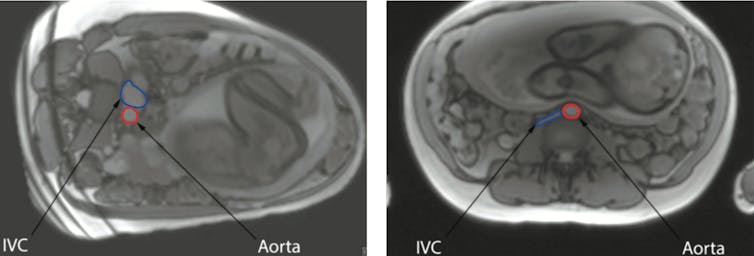

Recent research carried out at the University of Auckland has provided sophisticated evidence about how the mothers’ position influences blood flow. Results obtained using Magnetic Resonance Imaging (MRI) demonstrate the major vessel in the mother’s abdomen, the inferior vena cava, being compressed by the pregnant womb when she is lying on her back. This reduces flow through this vessel by 80%.

Although the mother’s circulation responds by increasing the flow through other veins, this does not fully compensate. The mother’s aorta, the main artery which carries oxygen-rich blood from her heart, is also partly compressed when the mother lies on her back. This decreases blood flow to the pregnant uterus, placenta and baby.